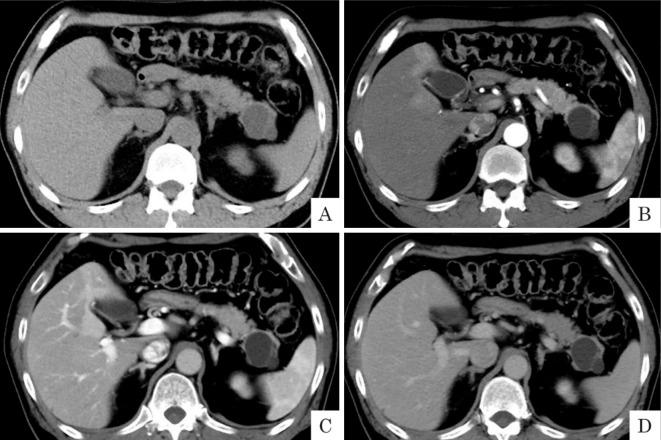

Follow-up computed tomography revealed a 40-mm pancreatic tail cyst in a 59-year-old man with type 1 diabetes mellitus. An intraductal papillary mucinous neoplasm was suspected; mucinous cystic neoplasm (MCN) was not considered because the patient was a man. During follow-up, cyst infection occurred but was improved by conservative treatment. At the 24-month follow up examination, cyst nodules had developed, corresponding to an increase in the carbohydrate antigen 19-9 level. Mucinous cystadenocarcinoma (MCC) was diagnosed pathologically based on distal pancreatectomy. A diagnosis of male MCN/MCC is often delayed, which may lead to a poor prognosis. MCN infection is also rare and poorly recognized. We observed an atypical male case of MCN/MCC.

随访计算机断层扫描显示,一名59岁1型糖尿病男性患者的胰尾有一个40毫米的囊肿。怀疑为导管内乳头状黏液性肿瘤;由于患者为男性,未考虑黏液性囊性肿瘤(MCN)。随访期间发生囊肿感染,但经保守治疗后好转。在24个月的随访检查中,出现了囊肿结节,同时糖类抗原19-9水平升高。根据远端胰腺切除术的病理结果诊断为黏液性囊腺癌(MCC)。男性MCN/MCC的诊断往往延迟,这可能导致预后不良。MCN感染也很罕见且认识不足。我们观察到一例非典型男性MCN/MCC病例。